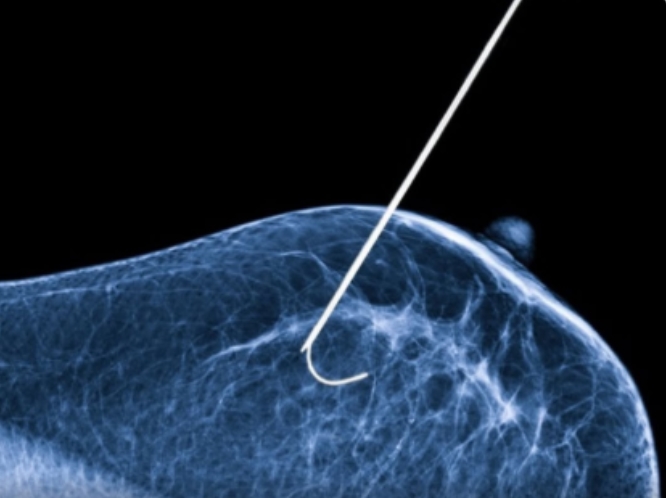

A crioablação é uma técnica já utilizada em países como Estados Unidos e Japão. Ela consiste na aplicação de nitrogênio líquido diretamente no tumor, atingindo temperaturas de aproximadamente -140 °C. Esse congelamento forma uma espécie de esfera de gelo que destrói as células cancerígenas.